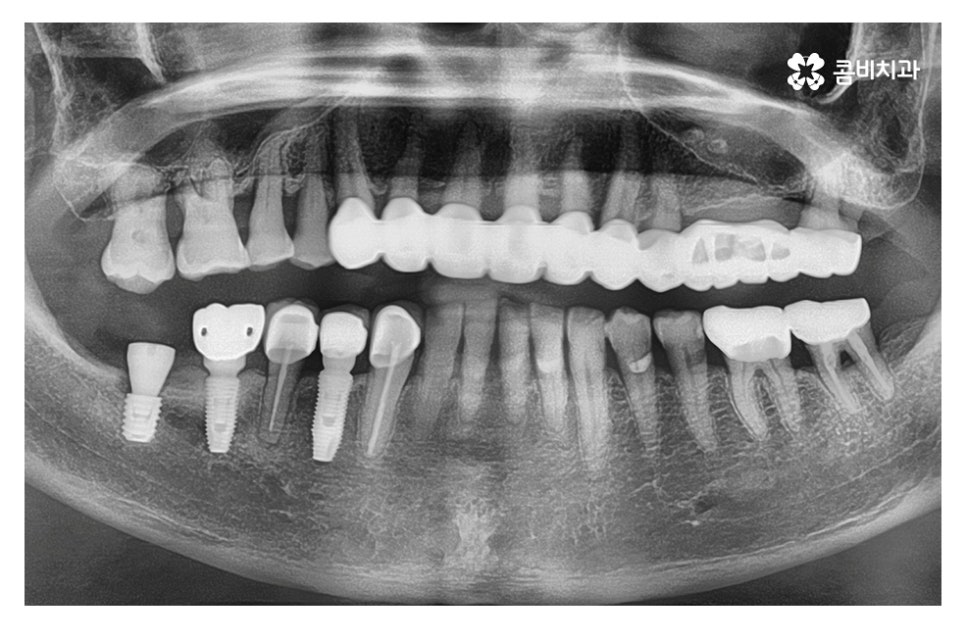

3차 수술에 보철물을 장착하여 임플란트 시술이 마무리되며

치료가 마무리된 후에는 약 1년 정도는 충분히 안정기를

거치면서 임플란트 부작용에 주의하도록 청결관리와

평소 생활 습관에 있어서도 각별한 주의가 필요할 수 있어요.